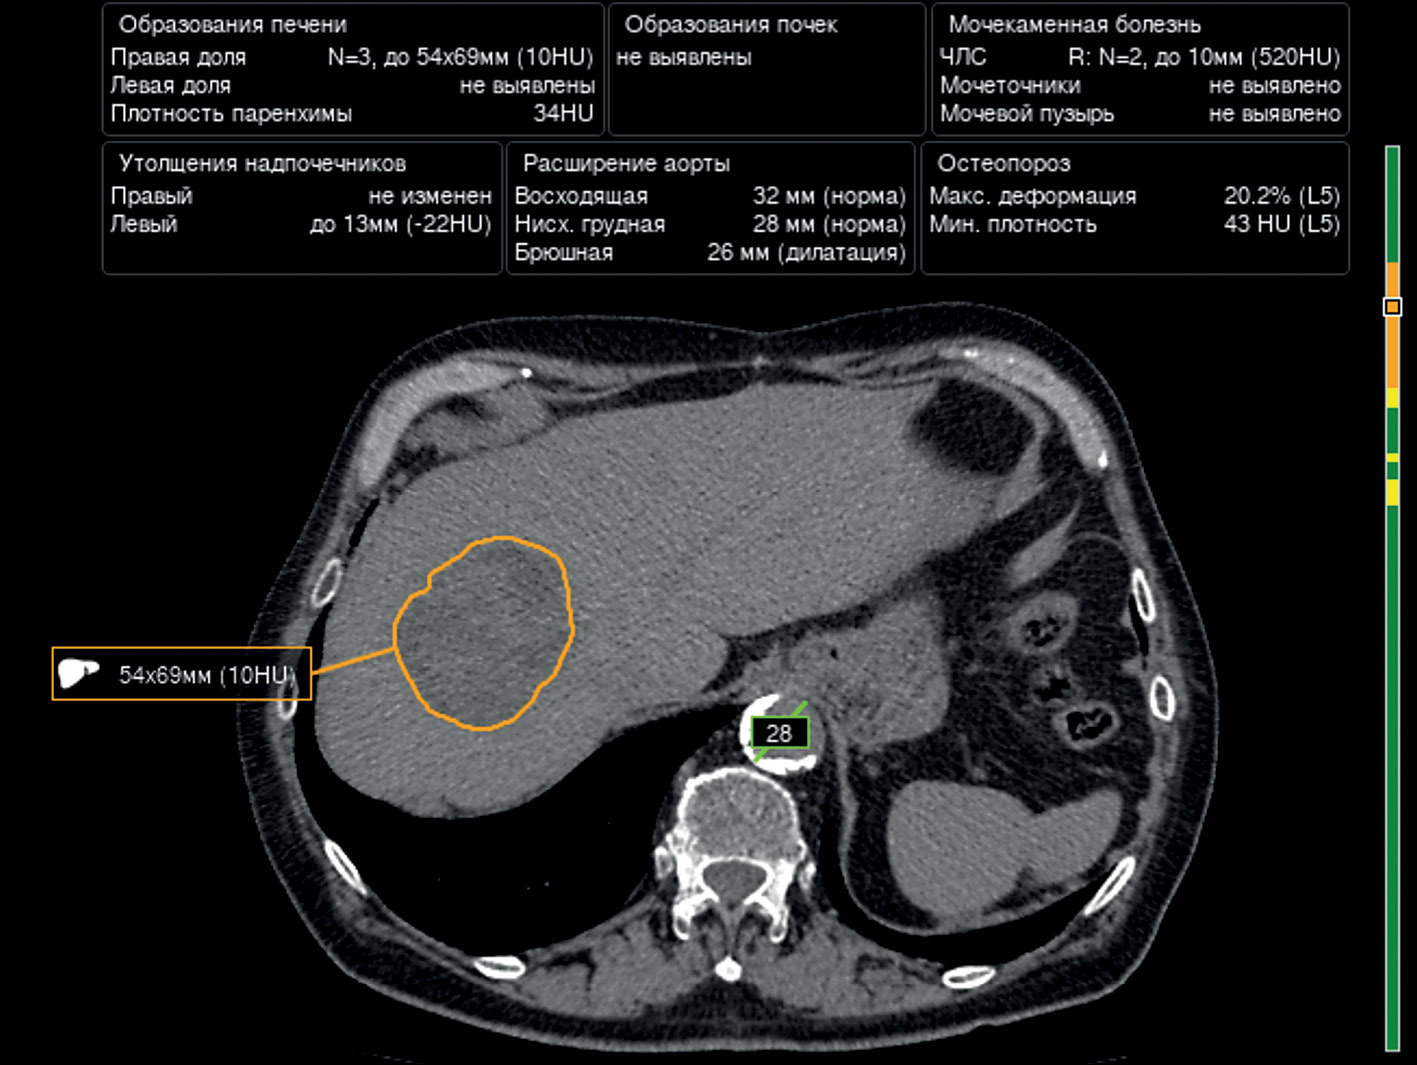

Prospects of using computer vision technology to detect urinary stones and liver and kidney neoplasms on computed tomography images of the abdomen and retroperitoneal space

Resumo

The article presents a selective literature review on the use of computer vision algorithms for the diagnosis of liver and kidney neoplasms and urinary stones using computed tomography images of the abdomen and retroperitoneal space. The review included articles published between January 1, 2020, and April 24, 2023. Pixel-based algorithms showed the greatest diagnostic accuracy parameters for segmenting the liver and its neoplasms (accuracy, 99.6%; Dice similarity coefficient, 0.99). Voxel-based algorithms were superior at classifying liver neoplasms (accuracy, 82.5%). Pixel- and voxel-based algorithms fared equally well in segmenting kidneys and their neoplasms, as well as classifying kidney tumors (accuracy, 99.3%; Dice similarity coefficient, 0.97). Computer vision algorithms can detect urinary stones measuring 3 mm or larger with a high degree of accuracy of up to 93.0%. Thus, existing computer vision algorithms not only effectively detect liver and kidney neoplasms and urinary stones but also accurately determine their quantitative and qualitative characteristics. Evaluating voxel data improves the accuracy of neoplasm type determination since the algorithm analyzes the neoplasm in three dimensions rather than only the plane of one slice.